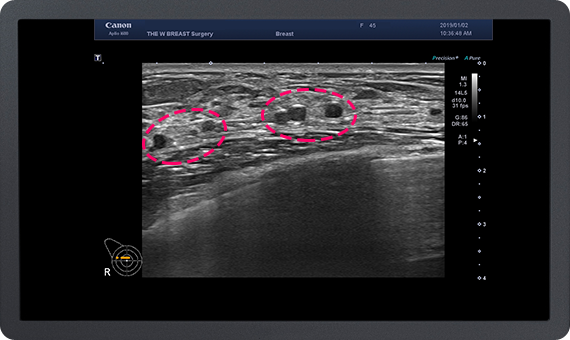

가슴지방 이식 수술 후 발생하는 가장 많은 부작용은

지방 낭종과 석회화입니다.

이에 대해 많은 경험을 가진 THE W 유방센터에서는

지방 이식 후 발생한 지방낭종과 석회화의 제거가 가능하며,

지속적인 유방암 추적이 가능합니다.